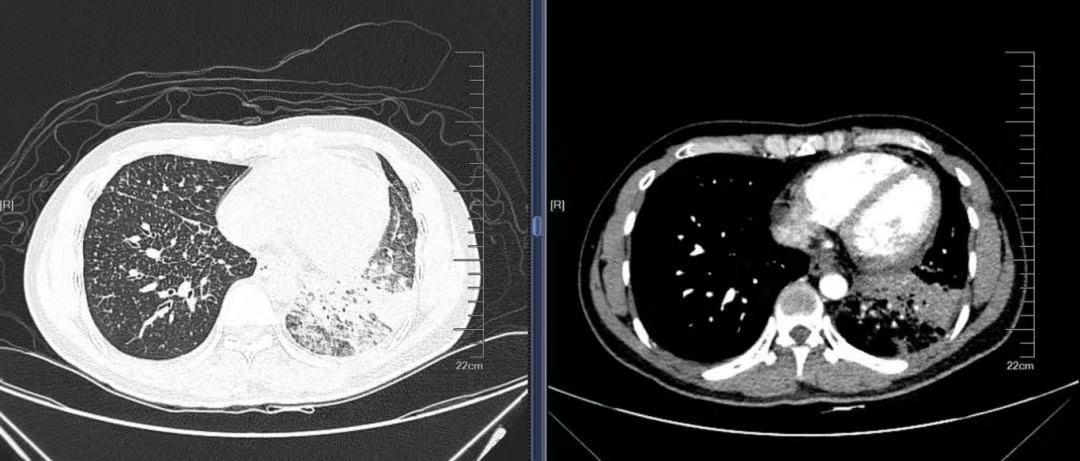

入院后,广州市花都区人民医院呼吸与危重症医学科团队首先为患者复查胸部CT,对比外院既往检查影像发现,其肺部病灶较前明显增多。通过全面排查,患者无发热、咳痰等明显感染症状,也无低热、盗汗、乏力、体重下降等结核中毒表现,同时否认粉尘、过敏原接触史,常见的感染、过敏相关病因被暂时排除。而肿瘤标志物检查显示相关指标升高,结合影像学特征,团队高度警惕肿瘤合并癌性淋巴管炎的可能,明确病理诊断成为诊疗关键。